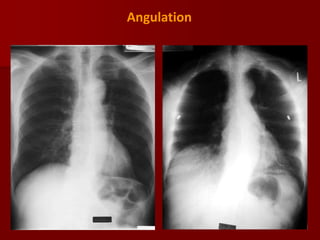

Angulation:

With the patient in a more lordotic projection and in

Apicogram the clavicles will project superiorly relative

to the upper thorax again causing some distortion of

the normal mediastinal anatomy.

With the lordotic projection of the ribs assume a

more horizontal orientation.

Occasionally a lordotic x ray can be obtained

intentionally to better visualize structures in the

thoracic apex obscured by overlying boney

structures.

Angulation